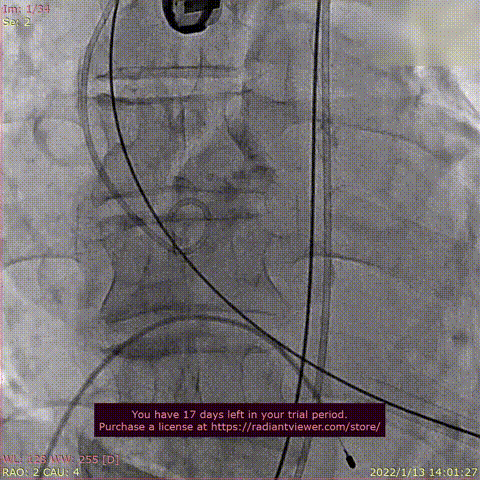

术前DSA造影